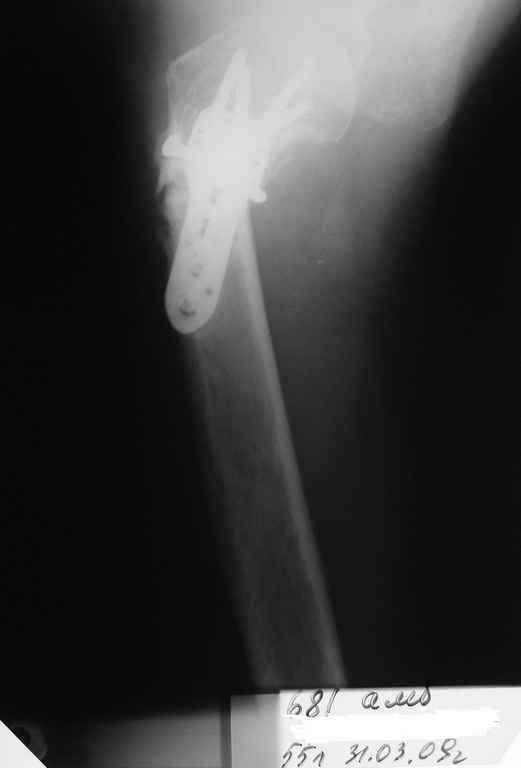

Пациентка Б.1953 г.р., врач-терапевт. Травма 27.11.08г. Падение с высоты роста. Выявлен закрытый не осложненный оскольчатый перелом хирургической шейки левого плеча со смещением. 02.12.08г. оперирована. Выполнена открытая репозиция и остеосинтез пластиной LCP Деост с дополнительной фиксацией отдельно лежащего фрагмента винтом. Послеоперационный период протекал без особенностей, заживление раны первичным натяжением. Швы сняты через 10 дней. Иммобилизация левой верхней конечности клиновидной подушкой 4 недели. По окончании срока – рентген-контроль и умеренная разработка плечевого сустава. В течении месяца функция левого плечевого сустава восстановилась удовлетворительно: поднятие руки до 110 гр., отведение - 90 гр. и до 110 гр. отведение с лопаткой. Отведение руки назад – 20 гр. Наружная и внутренняя ротация – 20 гр. Пациентка по настоянию самостоятельно вышла на работу. 27.03.09 при контрольном осмотре жалоб не предъявляет, болевой синдром в левом плечевом суставе отсутствует. Отведение плеча активно до 90 гр, пассивно с лопаткой до 110 гр., поднятие – 110 гр, отведение назад 20 гр, наружная и внутренняя ротация по 20 гр. На контрольных рентгенограммах отмечается смещение металлоконструкции, ротация головки плеча с приведением дистального отломка на 13 гр. и смещением к зади на 30 гр. Рентгенограммы прилагаются. Ваш взгляд на дальнейшую тактику лечения пациентки?

Уважаемый Евгений, похоже, что первый и второй Р-снимки выполнены несколько в разных положениях(ротация) плечевой кости, в связи с этим создается впечатление смещения пластины. Остеосинтез выполнен при угловом смещении отломков.Таковым и остался. Данная ситуация была бы очевидна гораздо раньше, если бы при контрольной Р-графии были выполнены снимки в 2-х проекциях.(Не в обиду, сам иногда выполняю только один).

Рентгенограммы действительно с дефектом укладки, но интраоперационная репозиция, можете поверить, была удовлетворительная как в акcиальной, так и в сагиттальной плоскостях. Интраоперационная рентгенограмма прилагается, хотя укладка тоже на ахти. По тактике - разделяю Ваше мнение об отсутствии необходимости реостеосинтеза, а тем более об эндопротезировании, хотя это все было предложено пациентке ведущими ортопедами-травматологами России.